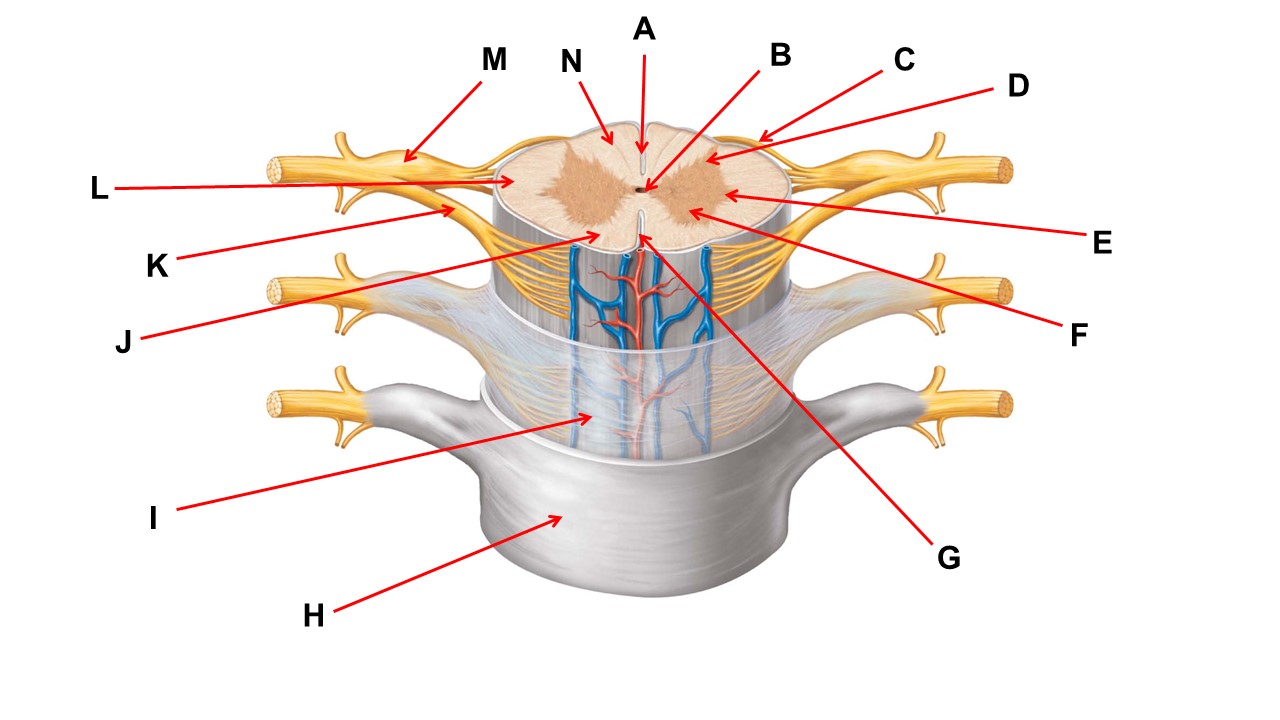

Name the region of tissue surrounding the tip of arrow E.

lateral horn

Name the region of tissue surrounding the tip of arrow B.

dorsal horn

Name the structure at the tip of arrow K.

ventral root

Name the region of tissue surrounding the tip of arrow J.

ventral column

Name the layer at the tip of arrow I.

arachnoid mater

Name the region of tissue surrounding the tip of arrow E.

lateral horn

Name the region of tissue surrounding the tip of arrow N.

dorsal column

Name the deep groove at the tip of arrow G.

anterior median fissure

Which structure(s ) would be found in the area at the tip of arrow D.

cell bodies of interneurons

Name the region of tissue surrounding the tip of arrow E.

ventral horn

Name the region within bracket G.

gray commisure